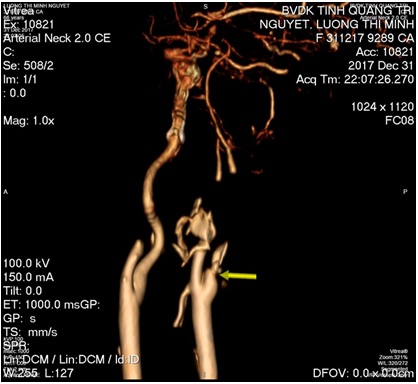

+ MSCT mạch máu não: Tắc hoàn toàn động mạch cảnh trong bên trái.

- B/N được chuyển Đơn nguyên DSA tiến hành can thiệp hút huyết khối mạch máu não

Hình: ĐM cảnh trong trái trước và sau lấy huyết khối (còn tắc M1 trái)